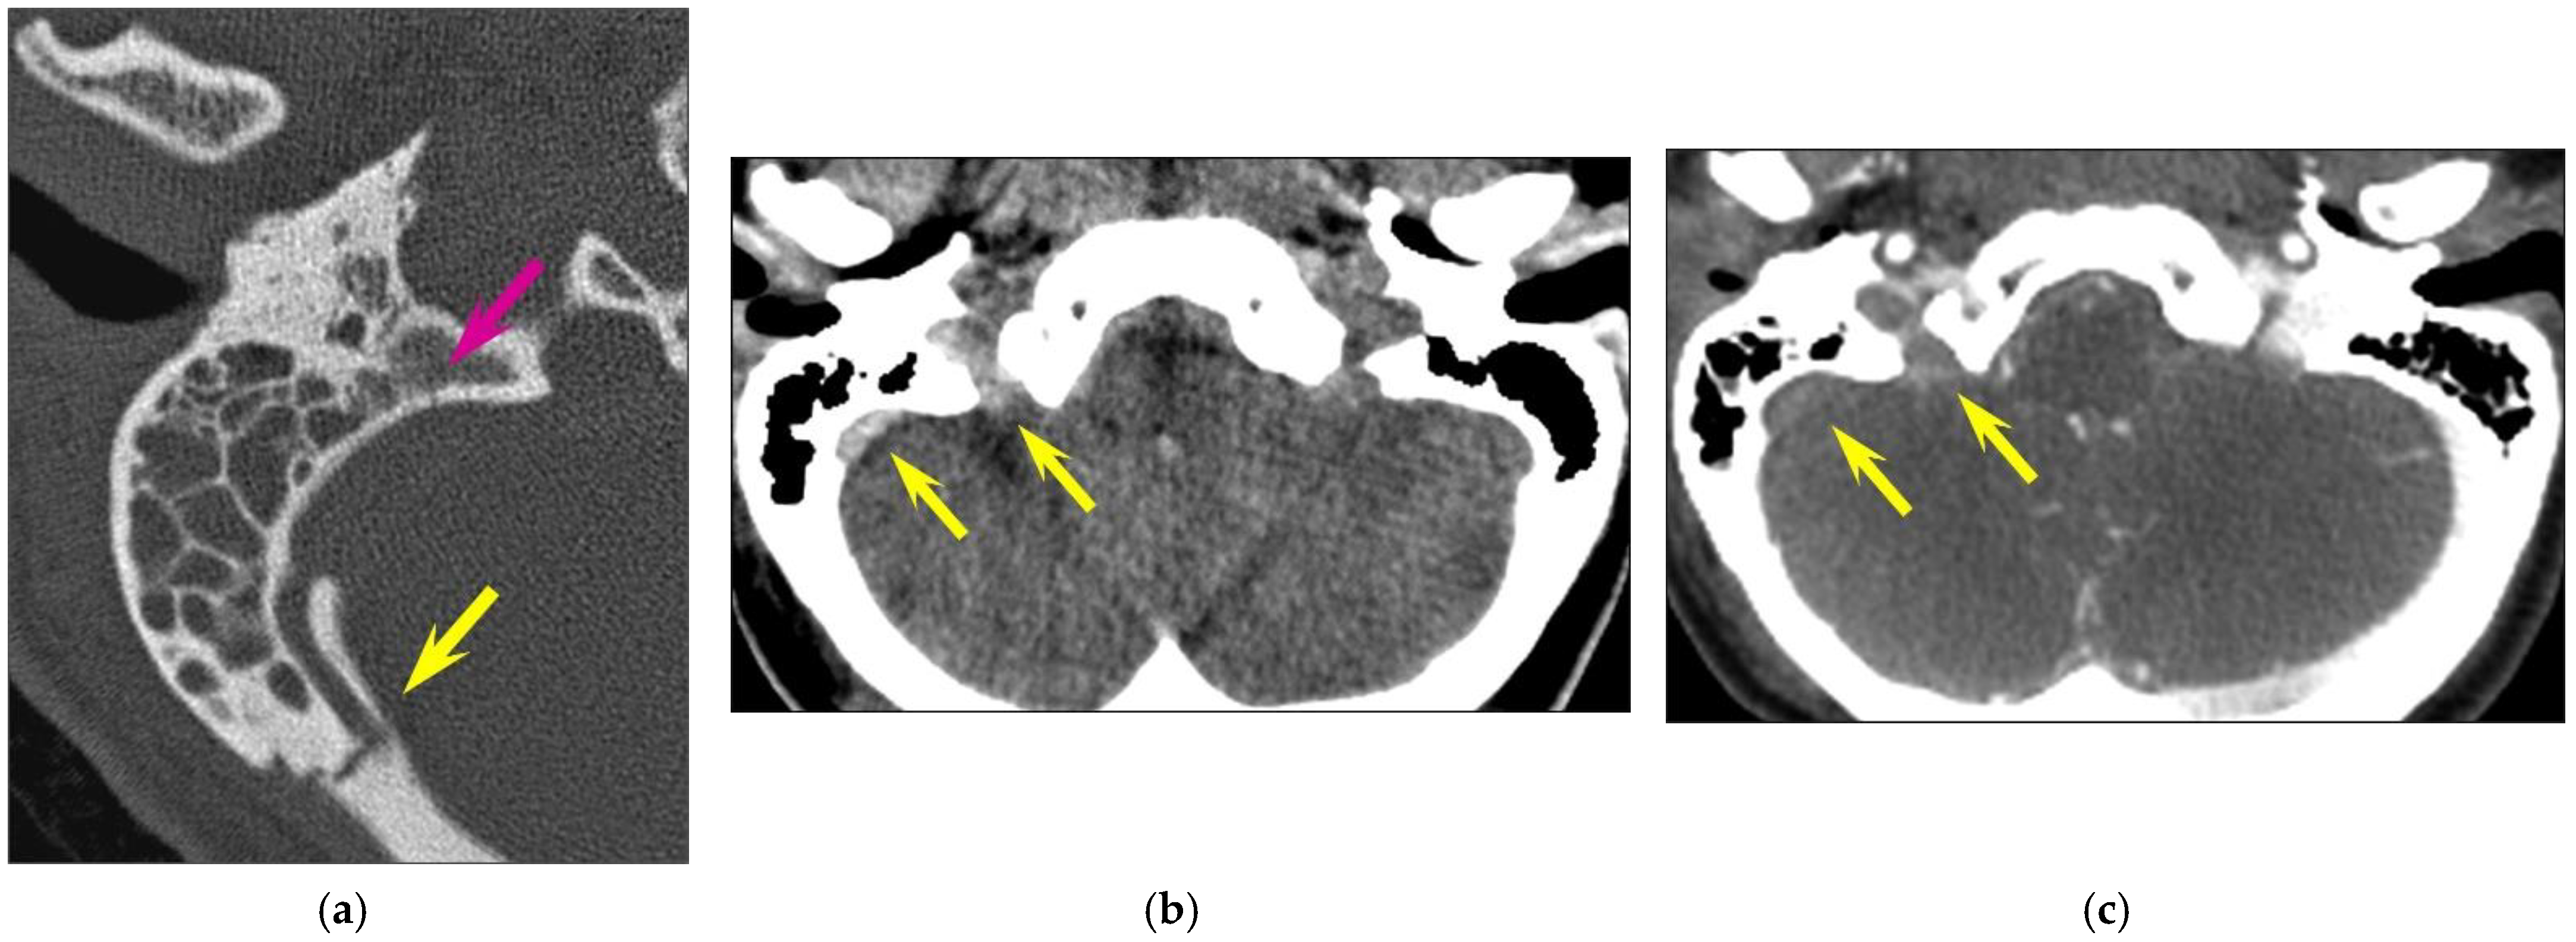

Figure 1. Inner ear injuries. A transverse fracture in an 84-year-old woman with otorrhagia after a fall. CT of the right temporal bone; (a) axial plane; (b) coronal plane. (a) Axial plane: The fracture line extends inferiorly from the aqueduct of the vestibule (yellow arrow) to the vestibule, with associated pneumolabyrinth (green arrow). (b) The fracture line (yellow arrow) also involves the jugular foramen (asterisk) and the superior semicircular canal (blue arrow).

In total, fractures involved the bony labyrinth in 11 cases and extended into the following structures: semi-circular canals (posterior semi-circular canal, n = 3; superior semi-circular canal, n = 2), vestibule (n = 3), cochlea (n = 1) and the vestibular aqueduct (n = 2). Involvement of the internal auditory canal was seen in two cases. Fracture lines extended into the petrous apex in 10/126 (7.9%) of all temporal bone fractures, and fractures along the osseous structures surrounding the facial nerve were seen in 8/126 (6.3%) cases. The fractures lines involved the geniculate fossa in four cases (Figure 2), the facial nerve canal in the tympanic cavity in two cases and the bony structure surrounding the second genu of the facial nerve in two cases, respectively. Air in the tympanic facial canal without a visible fracture line was present in one case.

Otic capsule fractures were rare in our series (4.8%). These data are confirmed by the literature, with a prevalence of around 5% in most series (2.5% [11], 5.6% [13], 5.8% [10], 7% [9], and 18.6% [8]. Pneumolabyrinth is the second important sign and can sometimes present isolated, as in one of our cases. Pneumolabyrinth typically presents as air bubbles within the vestibule, semi-circular canals or cochlea. It is considered a sign of a traumatic perilymphatic (labyrinthine) fistula which corresponds to an abnormal communication between the fluid-filled inner ear and the air-filled middle ear. Although patients usually present with sensorineural hearing loss, vertigo or tinnitus, perilymphatic fistula is often overlooked upon initial clinical examination due to the predominance of neurological symptoms in the emergency situation [19]. As perilymphatic fistulae can decompensate by efforts with increased pressure, early detection, patient counseling and/or surgical intervention are essential to avoiding irreversible hearing loss. Data regarding the true prevalence of pneumolabyrinth in temporal bone trauma are scarce and contradictory; some authors have suggested that it may occur in 8% of all temporal bone fractures and in 50% of otic capsule fractures [20]. However, a review of the international literature from 2014 found only 14 reported cases of pneumolabyrinth, most of which were associated with transverse temporal bone fractures (10/14 cases), and the authors concluded that pneumolabyrinth in the setting of temporal bone trauma is a rare phenomenon [21]. In our series, all otic capsule fractures had associated pneumolabyrinth and, in one case, it was only the presence of pneumolabyrinth—without a clearly visible fracture line—that suggested otic capsule involvement.